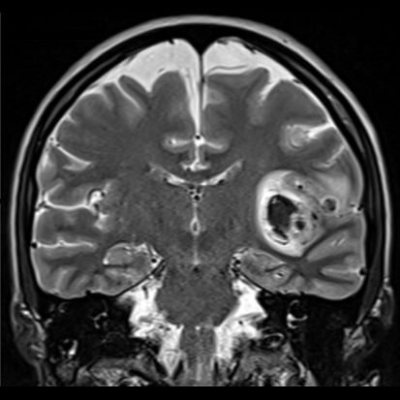

- Aksiyel (A) ve koronal (B) T2A görüntülerde sol insüler bölgede MCA M2 segmenti düzeyinde nodüler düşük sinyalli alanlar (oklar) ve vazojenik ödem ile uyumlu hiperintens alanlar (yeşil oklar) izleniyor.